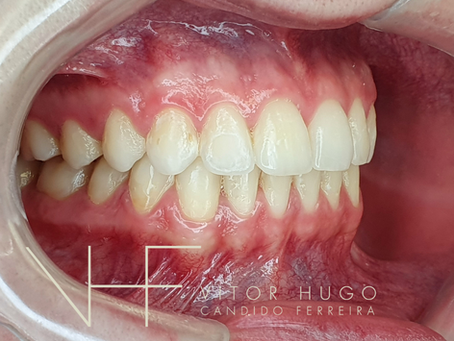

Por que tirar os dentes do Sisos - Terceiros Molares

"Doutor, mas por que devo tirar os meus sisos?" Autor: Dr Vitor Hugo Candido Ferreira Especialista, mestre e professor em Cirurgia...